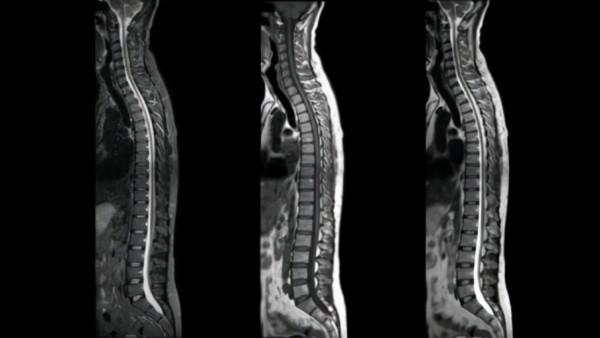

MR 5300大(55 釐米)視場提供了更大的解剖覆蓋範圍,同時其強大的AI驅動掃描方法和易於定位的超輕量dStream Breeze線圈相結合產生優質的影象質量,尤其是在對具有挑戰性的解剖結構,如脊椎、腹部進行成像時比。透過簡化、自動化捕獲高質量影象所涉及的複雜臨床和操作任務,MR 5300提高了放射科輸出的一致性和生產力,有助於提高患者滿意度和轉診率,其無氦操作使其適用於門診和專門的放射科。